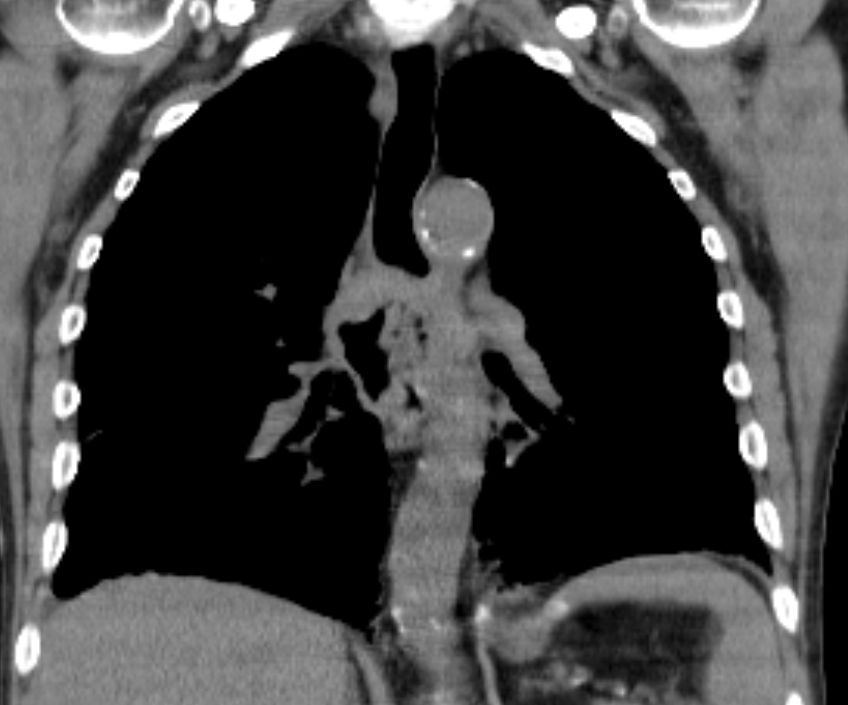

CT Infiltration des oberen Mediastinums. Flottierender Thrombus in der Vena cava superior.